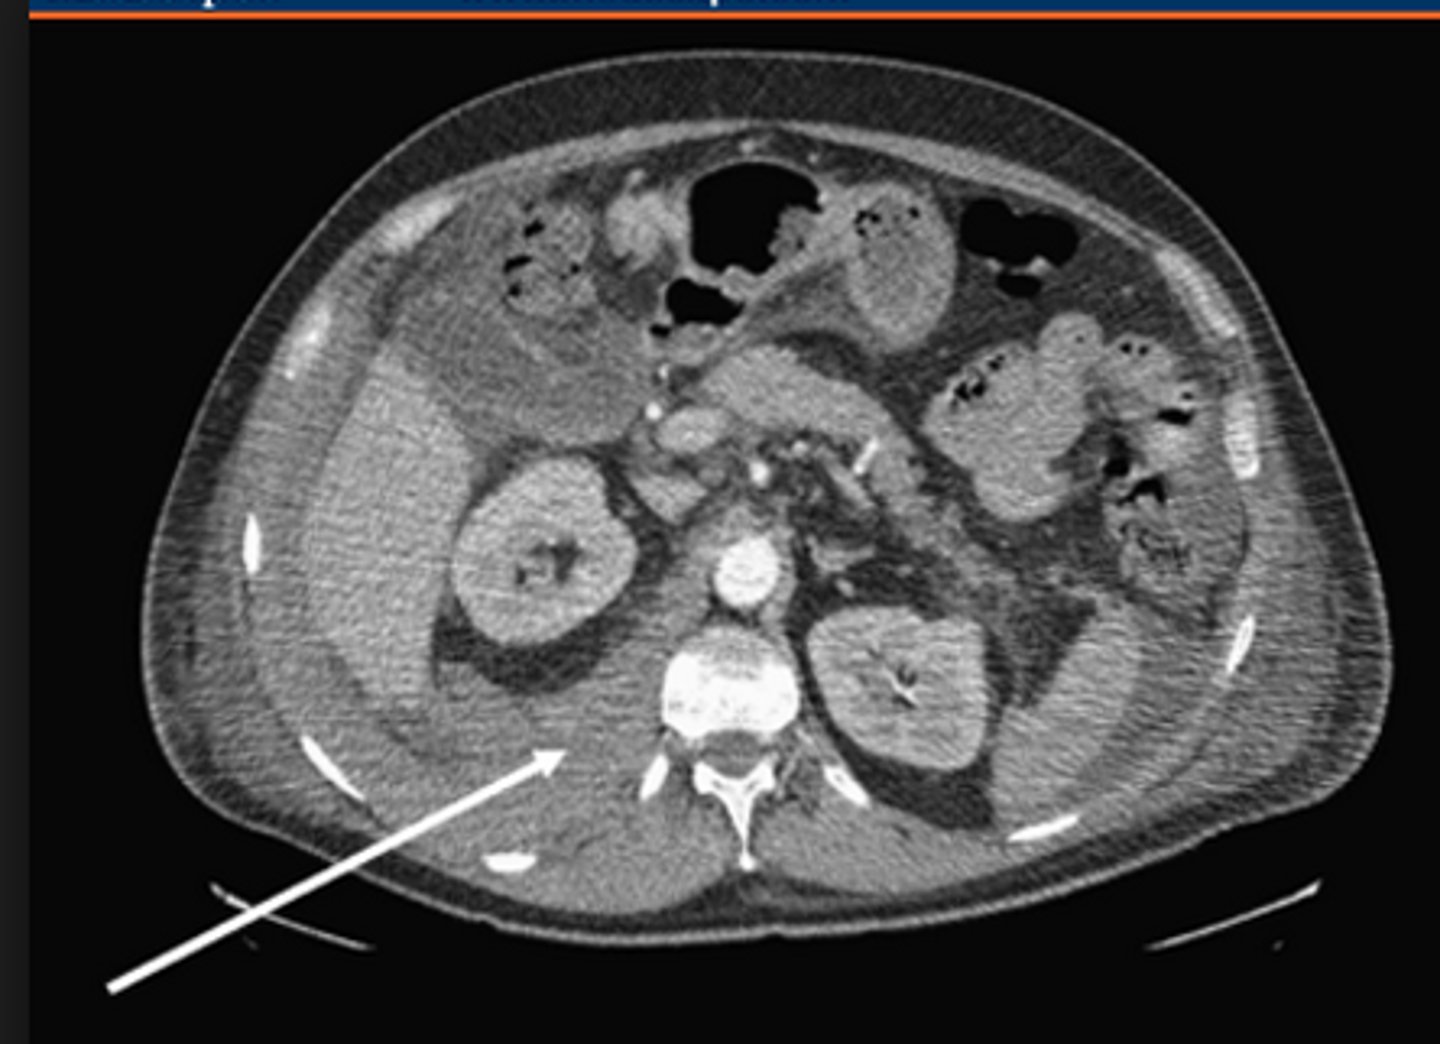

Acute pancreatitis by hypotension is through to arise from intravascular volume loss 2/2 ___.

Local and systemic vascular endothelial damage

- > vasodilation, INC vascular permeability, and plasma leak into the retroperitoneum, resulting in systemic hypotension

tx: supportive care with several Liters of IV fluid to replace the lost intravascular volume